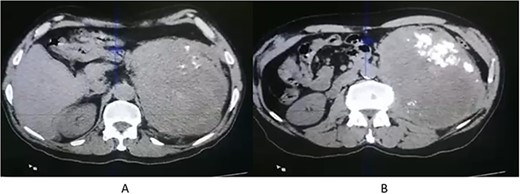

A 71-year-old Jordanian male with a known case of hypertension presented with left flank pain for 3 months. An abdominal computed tomography (CT scan) revealed a huge, 20 × 12 × 7 cm left renal solid mass, disrupting the upper two-third of renal parenchyma, with thick dystrophic calcifications, and causing displacement of the surrounding bowel structure (Fig. 1). Clinically, a renal tumor was suspected and left nephrectomy was performed. The patient recovered well after the operation without any surgical complications.

CT scan axial (A, B) showing left renal solid mass, disrupting the upper two-third of renal parenchyma, with thick dystrophic calcifications (B).